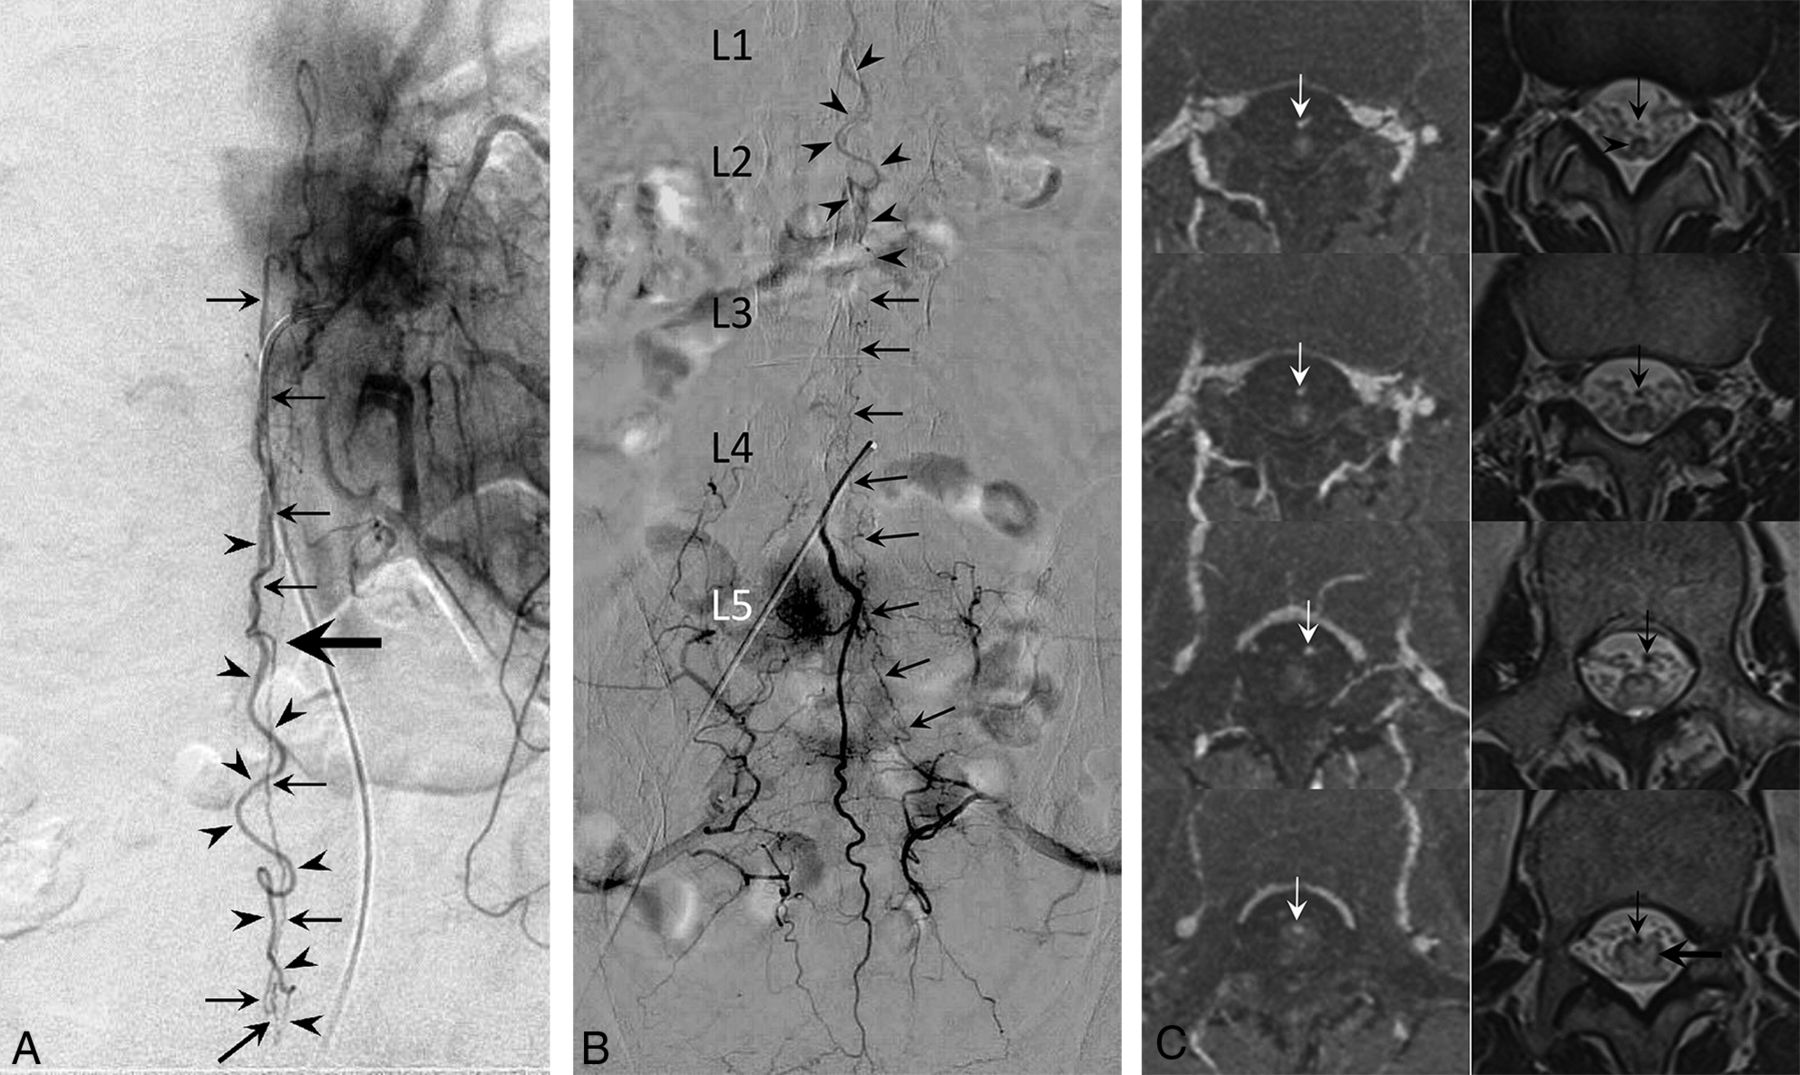

A, Angiogram of the left T11 intercostal artery in anteroposterior view demonstrates a posterior spinal artery supplying the anterior spinal artery (arrows) via the vasa corona. The ASA extends caudally to form a fistula at the L3 level (oblique arrow). The ascending draining vein shows a characteristic wavy pattern (arrowheads). Note the change in course and caliber of the descending ASA at the apex of the conus medullaris, suggesting a switch in the ASA to a radicular artery (large horizontal arrow). B, Medial sacral artery angiogram in anteroposterior view demonstrates anastomotic opacification of the radicular artery (arrows) from the left S1 lateral sacral artery supplying the L3 level AVF. The same draining vein seen in A is detected in this study (arrowheads). The L3 AVF in this patient has a dual supply from the ASA and an S1 radicular artery. C, Serial thin-section gadolinium-enhanced T1WI (left column) and T2WI (right column) arranged in caudal (upper) to cranial (lower) order show the draining vein (arrows) is off the cord at the apex of the conus medullaris (arrowhead). The draining vein eventually merges with the spinal cord at the L1 level (large horizontal arrow). This finding suggests that the draining vein is a radicular vein.